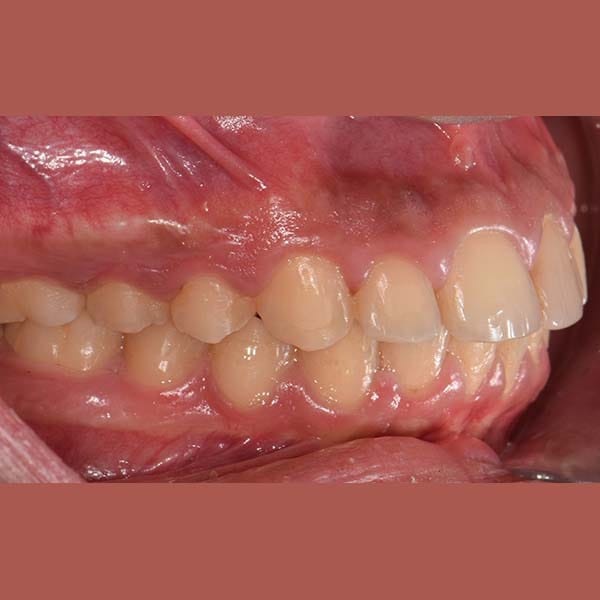

AFTER

كما تظهر الصور، تم تصحيح البروز وتراجع الفك السفلي بنجاح. أصبح بإمكان صديقنا الآن أن يبتسم بثقة، والأهم من ذلك، أن يأكل ما لذ وطاب من دون أي مشاكل في القضم.